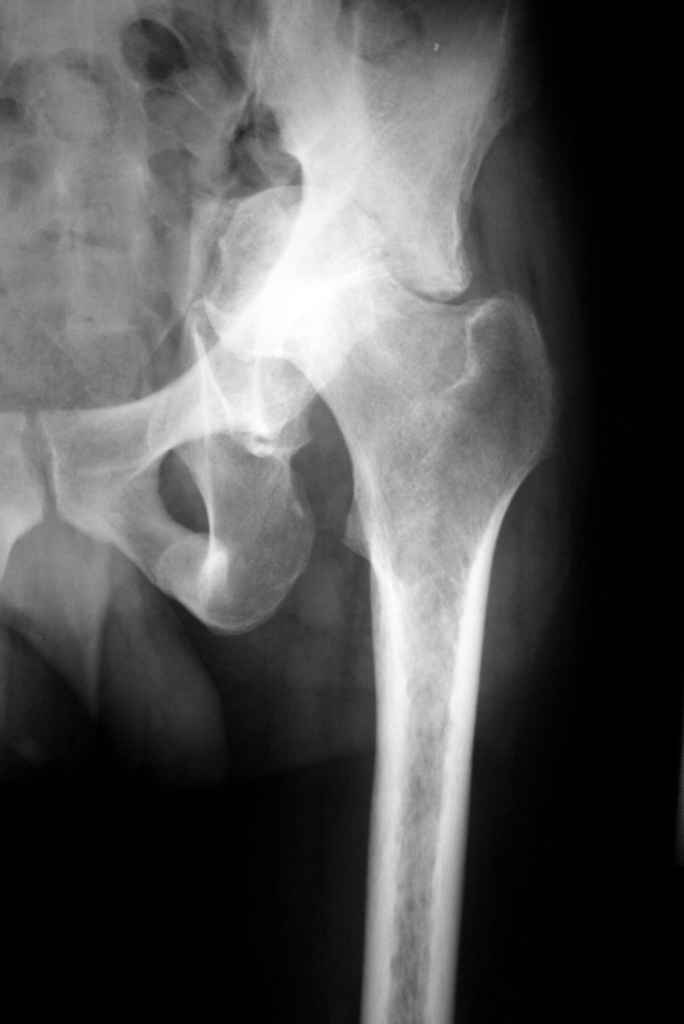

К нам обратился житель Казахстана с застарелым вывихом бедра. Травма год назад, вместо синтеза заднего края казахскими умельцами установлена клинковая пластина, через 6 мес удалена. Больной ходит с тростью,сгибание в т-б 90, разгибание 170, укорочение 5 см, боли не выражены, анальгетиками не пользуется. Настроен на эндопротезирование в клинике, где есть опыт подобных операций (возможно за рубежом).Наш план: аппарат таз-бедро, постепенное низведение бедра, "октопус" с пластикой. Но с такими большими дефектами мы не сталкивались.Есть вариант сначала аппарат, затем реконструкция впадины, протез обычный через 4-6 мес.Есть мнение не восстанавливать длину. Будем признательны за полезные советы. Было бы интересно посмотреть пример.

Кстати, судя по рентгенограммам и КТ истинная разница в длине ног не столь велика, укорочение, главным образом, за счет контрактур.